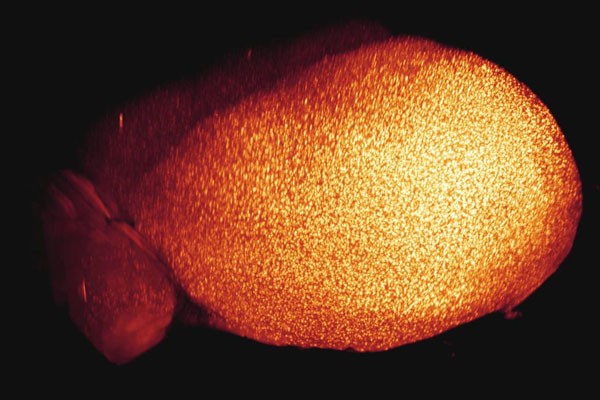

Die hellen Punkte sind Beta-Amyloid-Plaques im Gehirn einer Maus. Sie werden für die Entstehung der Alzheimer-Krankheit verantwortlich gemacht.

Wien (TU). Ins Gehirn hineinschauen zu können ist ein alter Traum der Wissenschaft. Moderne bildgebende Techniken wie die Magnetresonanztomografie zeigen Gehirne zwar sogar bei der Arbeit, sind aber noch sehr weit von der Darstellung einzelner Hirnzellen entfernt. Um zu sehen, wie sich die Nervenzellen verzweigen und mit ihren Nachbarzellen in Kontakt treten, sind die HirnforscherInnen bisher auf zweidimensionale anatomische Präparate angewiesen. Hans-Ulrich Dodt, Professor und Leiter der Abteilung Bioelektronik am Institut für Festkörperelektronik der Technischen Universität (TU) Wien, arbeitet seit knapp vier Jahren an einer völlig neuen Methode, Gehirne unter dem Mikroskop bis in kleinste Details zu analysieren. Dafür macht er beispielsweise komplette Mäusegehirne nahezu völlig durchsichtig. ,,Wir passen den Brechungsindex des Hirngewebes mit einer öligen Flüssigkeit so an die Umgebung an, dass die Gehirne transparent werden", erklärt er seine Methode.